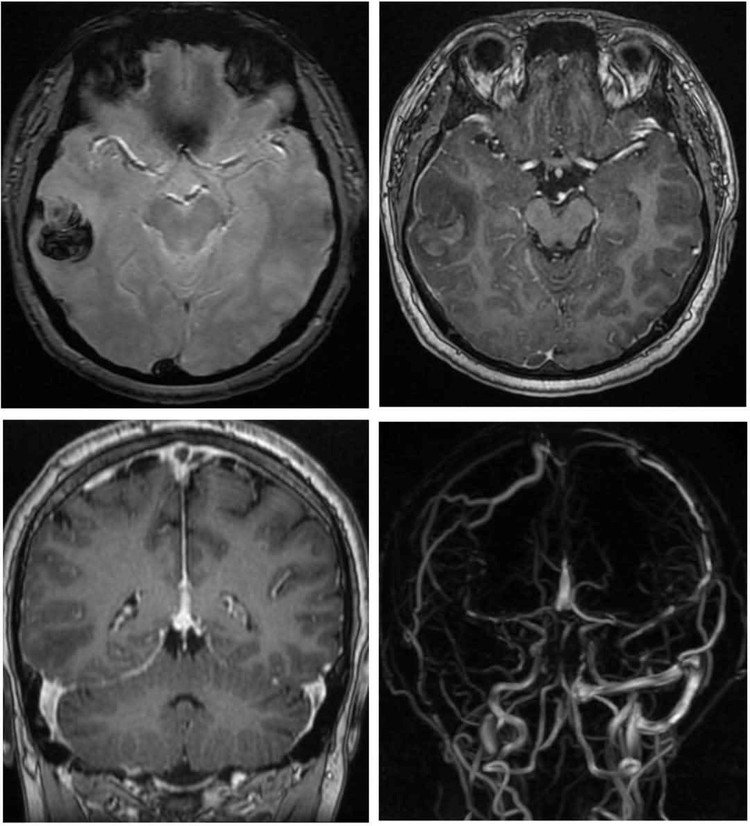

Khi kiểm tra thêm bằng bằng cộng hưởng từ (MRI) có bơm thuốc cản quang, các bác sĩ phát hiện huyết khối tại nhiều vị trí trong hệ thống tĩnh mạch não.

| Hình ảnh não của nam thanh niên 22 tuổi bị đột quỵ xuất huyết não do hút shisha liên tục trong một năm qua |